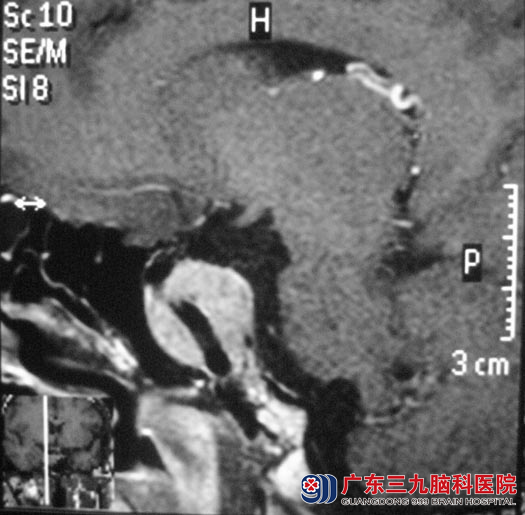

有朋友建议她来广州大医院进行治疗。内分泌检查提示泌乳素大于200ng/ml,生长激素高,头颅MR检查结果提示:鞍区占位性病变,考虑侵袭性垂体腺瘤,大小约2.0cm×2.1cm×2.2cm。

广东三九脑科医院垂体瘤诊疗中心 鲁明主任向周女士解释:她的不孕和这个肿瘤有密切关系。完善检查后,鲁明主任主刀,在全麻下行经鼻碟入路垂体瘤切除术,术中可见骨质较硬、厚,血供丰富,导航再次定位,切开硬膜,见肿瘤呈微黄色,质软、脆,易剔除,在显微镜下予肿瘤切除,术后周女士恢复很快,复查内分泌结果都较术前下降。病理结果:垂体腺瘤。